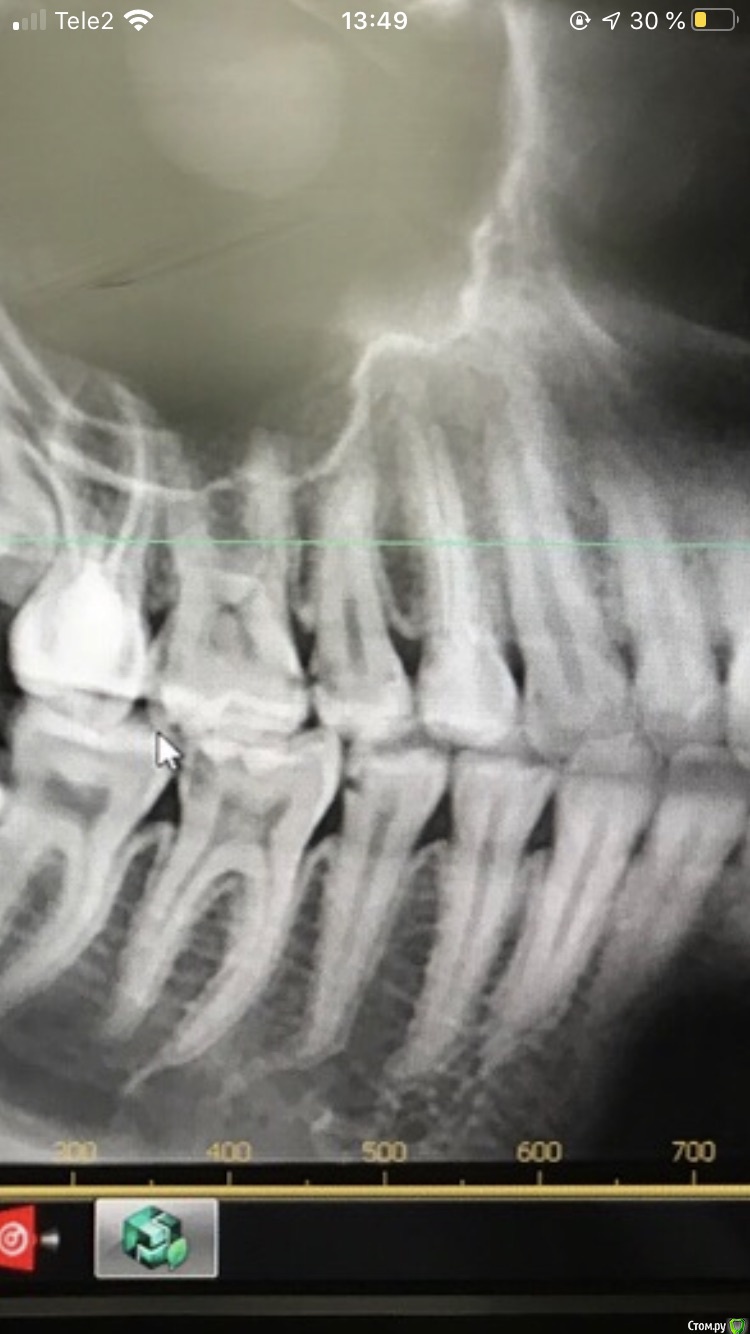

Marialalala Опубликовано 4 июня, 2020 Поделиться Опубликовано 4 июня, 2020 (изменено) Здравствуйте, лечу зубы, мой врач уходил в длительный отпуск, решила не терять время и сходила пролечила два зуба к врачу по отзывам в интернете. Принесла снимок этому врачу, он пролечил, зубы начали реагировать, я сходила сделала ещё снимок (в ближ.клинику), отправила этому врачу и описала жалобы, он сказал, что по снимку все хорошо, на мой вопрос о том, что за затемнение осталось в зубах, врач сказал, что это изолирующая прокладка, но я сразу скажу, что со слов врача и по акту оказания услуг мы лечили средний кариес, который разве предполагает изолирующую прокладку?. Врач сказал, что все хорошо, но если разболится, то приходите. Болеть вроде перестало, вышел с отпуска мой постоянный врач, мы начали лечить другие зубы, более насущные и как дошла очередь до этих зубов, он сразу по снимку сказал, что пролечено не до конца, необходимо переделать, при работе подтвердил, что мягкий дентин остался, в 6 зубе В одной точке вскрылась пульпа, но не кровила, врач решил пока не удалять нервы и поставил пломбу, с надёжной, что все будет хорошо. Я пишу тому врачу из интернета о том, что зубы он пролечил не качественно и хочу вернуть деньги, врач здоровается и пишет фио главрача и его данные. Главрач мне пишет о том, что почему вы не пришли на перелечивание, я говорю о том, что какое перелечивание, ваш врач сказал, что все пролечено хорошо! Главрач с меня просит новое ОПТГ (в той же проекции, разве у ОПТГ разные проекции?) и просит прислать чек и акт за работу во второе своей клинике, я сначала согласилась, а потом посоветовалась с подругой юристом, которая сказала, чтобы я писала досудебную претензию и без всякий новый снимков и чеков со второе клиники, ведь есть снимок после их врача по которому все и так понятно. Как мне быть? Есть ещё такой момент, что своего постоянно врача я не хочу в это втягивать, писать им координаты клиникИ и т д, ну вот не хочу, я же имею на это право? Что мне делать, как всё-таки вернуть с них деньги? Снимки до лечения и после лечения временного врача прилагаю (разница в снимках пару месяцев). 46 и 45 зубы! Изменено 4 июня, 2020 пользователем Marialalala Ссылка на комментарий